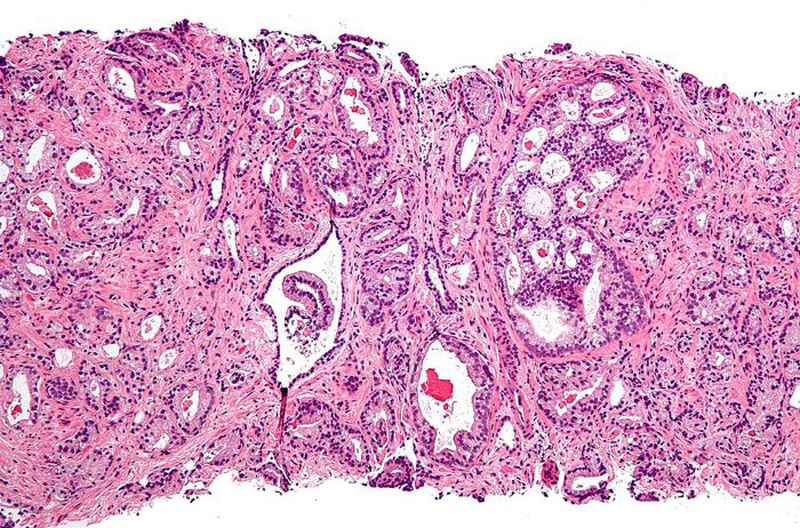

Tumore della prostata, bene la terapia chemio-free

La terapia “chemio-free”, con l'aggiunta della molecola abiraterone al trattamento ormonale standard, si conferma efficace nel mantenere stabile la malattia, e quindi allungare la sopravvivenza dei pazienti con tumore alla prostata metastatico alla diagnosi e ad alto rischio, con più del 50% dei pazienti ancora in vita a quarantuno mesi di follow-up.

Lo confermano gli ultimi dati, presentati al congresso dell'American Society of Clinical Oncology (ASCO), dello studio di fase III LATITUDE, studio effettuato su 1.200 uomini. La ricerca ha mostrato che abiraterone ha diminuito il rischio di morte del 36%.